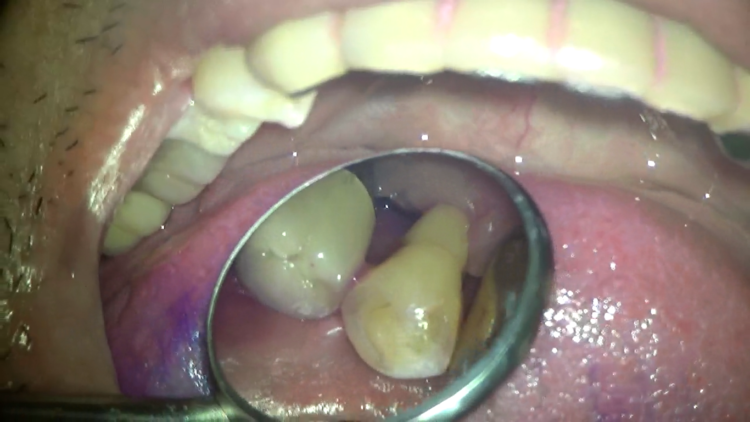

表側から通しただけなのに、ここまできれいになりました!!

ここからは、タフトブラシの出番です。

普通の歯ブラシでは当てにくくても、タフトブラシなら確実に狙って磨くことが出来ます。

普段の歯磨きで、どうしても苦手なところなどは、タフトブラシがおすすめです。